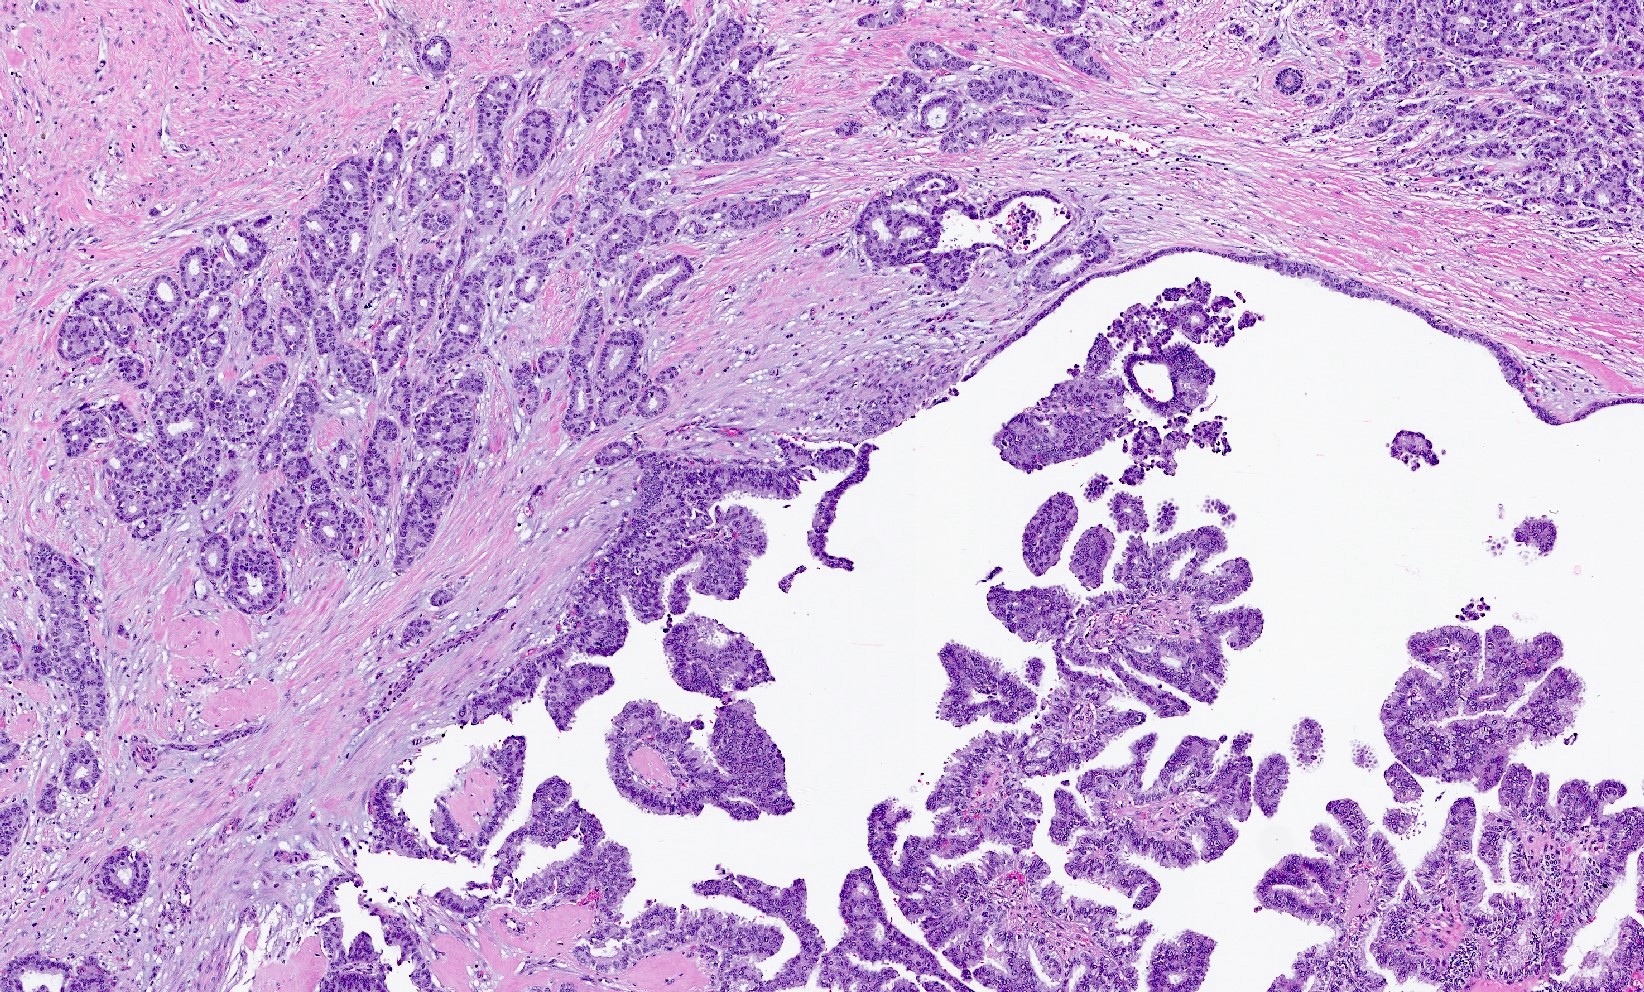

- Papillary tumor with pushing borders, may be within a cystically dilated duct, surrounded by a thick fibrous capsule (Histopathology 2008;52:20, Mod Pathol 2021;34:1044, Virchows Arch 2022;480:5)

- Delicate papillary fronds with fibrovascular cores lined by cuboidal to columnar epithelial cells with low to intermediate grade atypia

- Cribriform and solid architecture may be present

- Most show complete lack of myoepithelial cells along the papillae and around the periphery of the tumor (Am J Surg Pathol 2006;30:1002, Am J Surg Pathol 2011;35:1)

- Invasive carcinoma is defined as the presence of neoplastic cells infiltrating beyond fibrous capsule (Mod Pathol 2021;34:1044)

- Epithelial displacement / entrapment of neoplastic cells within capsule can occur and must be distinguished from true invasion beyond the fibrous capsule

Microscopic (histologic) images

Contributed by Kristen E. Muller, D.O. , Mariel Molina Nunez, M.D. and Julie Jorns, M.D. (Case #518)